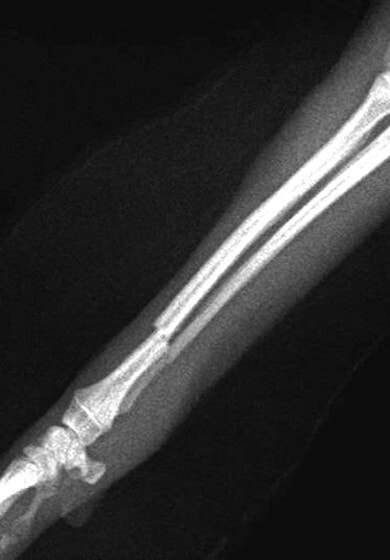

橈尺骨骨折 : 症例1 | 症例2 | 症例3 | 症例4 | 症例5 | 症例6 | 症例7

: 症例8 | 症例9 | 症例10 | 症例11 | 症例12 | 症例13 | 症例14

: 症例15 | 症例16 | 症例17 | 症例18 | 症例19 | 症例20 | 症例21